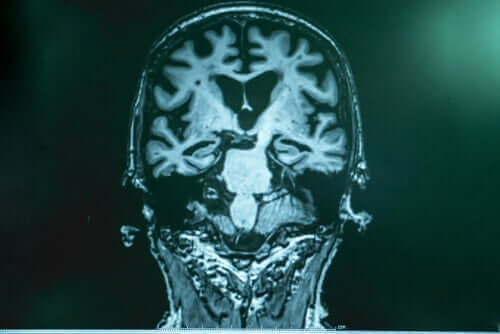

Le Docteur Lopera explique qu’il y a, dans la maladie d’Alzheimer, une sorte d’accumulation de “déchets” dans le cerveau. Ce déchet est composé d’une protéine appelée amyloïde.

Les fragments de cette dernière s’unissent et forment quelque chose comme une “substance visqueuse” qui s’accroche aux neurones et provoque une série d’échecs. L’autre partie des “déchets” est le tau, qui enveloppe le neurone, l’enferme et le tue. Tau est plus nocif.